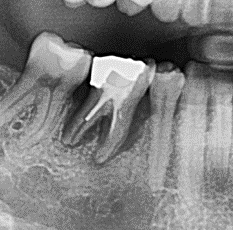

Hier sieht man das Problem:

Zerstörter Zahnhalteapparat – Die erste Abbildung zeigt einen Backenzahn mit einem ausgeprägten Knocheneinbruch. In der zweiten Abbildung ist der Knochenverlauf zum besseren Verständnis noch einmal durch eine rote Linie dargestellt. Die grüne Linie stellt den normalen Knochenverlauf im gesunden Zustand dar. Die Fläche zwischen beiden Linien entspricht dem Knochenverlust. Ursache für dieses Problem ist eine bakterielle Entzündung, die sogenannte Parodontitis. Diese kann den Zahnhalteapparat zerstören und führt unbehandelt letztendlich zum Zahnverlust.